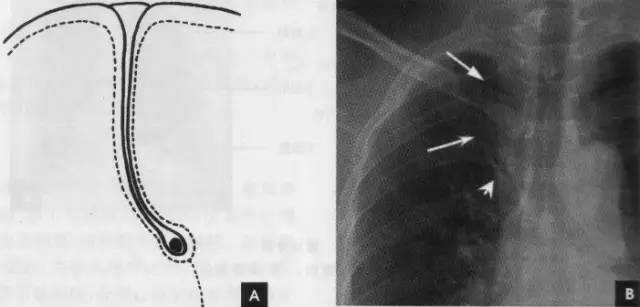

2、侧位肺门 侧位胸片上,两饲肺门阴影大部分重叠,若以侧位气管轴线为界,右肺门略信其前下,左肺门大部分在其后上。侧位肺门影前缘为右上肺静脉干形成的椭圆形阴影,前后径为2cm左右;中间纵行透亮区为气管及气管分叉,其内圆形透亮影表示支气管开口,右侧在上,左侧居下;后上缘为左肺动脉弓,下缘由两下肺动脉构成下行的树枝状影。因此,侧位肺门影似一尾巴拖长的“逗号”(如上右图):